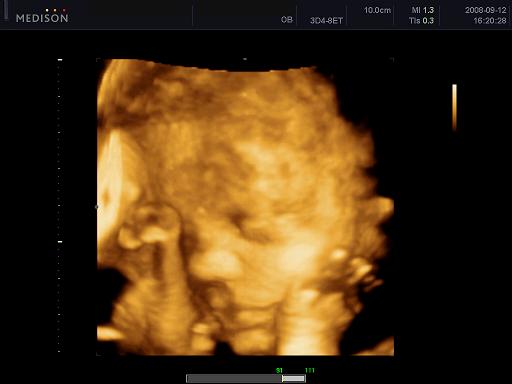

Baba neme: Én csak a szívem mélyén éreztem, hogy fiú lesz, férjem meg volt róla győződve, hogy ő fiút "csinált".